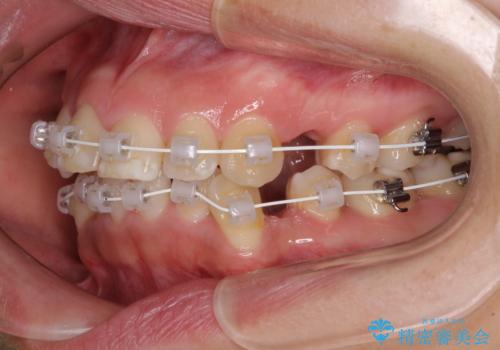

- 矯正装置

- 審美装置

- 1年8ヶ月

当初予定は2年半程度と伝えていましたが、2年にも満たない期間で治療を終えることができました。